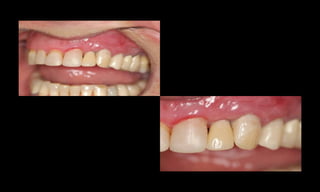

10-10-2005

Novembro de 2005

24-01-2006

Cone Morse